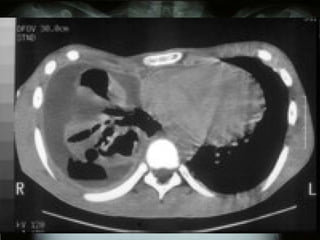

DIAGNÓSTICO POR  IMAGENOLOGÍA Oscar Asensio de la Cruza, Javier Blanco Gonzálezb, Antonio Moreno Galdóc, Javier  Pérez Fríasd, Antonio Salcedo Posadase, Lidia Sanz Borrellf Radiografía   PA y L :  hallazgo típico del derrame pleural:  obliteración del ángulo costofrénico posterior   que da una  imagen de menisco , bien notorio  >  de 175 ml de líquido .

RADIOLOGIA:  Detecta la presencia del derrame y sugiere su etiología  En la radiografía PA y lateral, el hallazgo típico del derrame pleural es la obliteración del ángulo costofrénico posterior (imagen de menisco). Un derrame masivo produce desviación contra lateral del mediastino; la causa más frecuente es la malignidad

RADIOLOGIA:  Se observan hallazgos atípicos: aplanamiento o desplazamiento en la cúpula  aumento de la distancia del diafragma a la burbuja gástrica (2 cm) u opacidad eliptoidea o &quot;pseudotumor&quot;. La proyección en decúbito lateral ayuda en casos de duda.  Importante cuando se va a puncionar (seguridad). .

RADIOLOGIA: Detectala presencia del derrame y sugiere su etiología En la radiografía PA y lateral, el hallazgo típico del derrame pleural es la obliteración del ángulo costofrénico posterior (imagen de menisco). Un derrame masivo produce desviación contra lateral del mediastino; la causa más frecuente es la malignidad

RADIOLOGIA: Seobservan hallazgos atípicos: aplanamiento o desplazamiento en la cúpula aumento de la distancia del diafragma a la burbuja gástrica (2 cm) u opacidad eliptoidea o &quot;pseudotumor&quot;. La proyección en decúbito lateral ayuda en casos de duda. Importante cuando se va a puncionar (seguridad). .